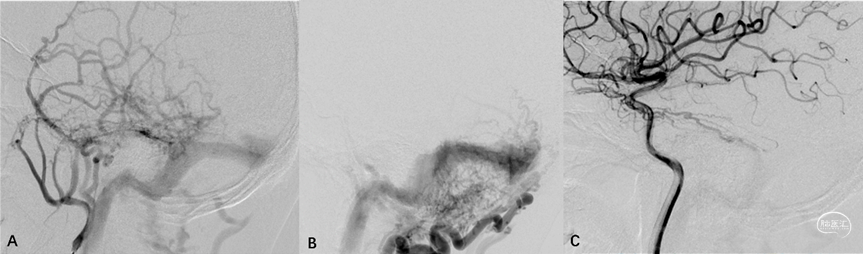

1.静脉窦型硬脑膜动静脉瘘(dural sinus type DAVF, DS-DAVF),以下简称窦型DAVF,即动-静脉移行起自硬膜固有静脉,主要通过硬膜血管汇集区(shunted pouch, SP)向静脉窦引流,软膜静脉可通过静脉窦逆流间接显影。影像学表现为静脉窦早于软膜静脉显影(图2)。

图2. 窦型DAVF的血管构筑与硬膜血管汇集区。侧窦区窦型DAVF,起自硬膜固有静脉系统向横-乙交界区汇聚(A-C)